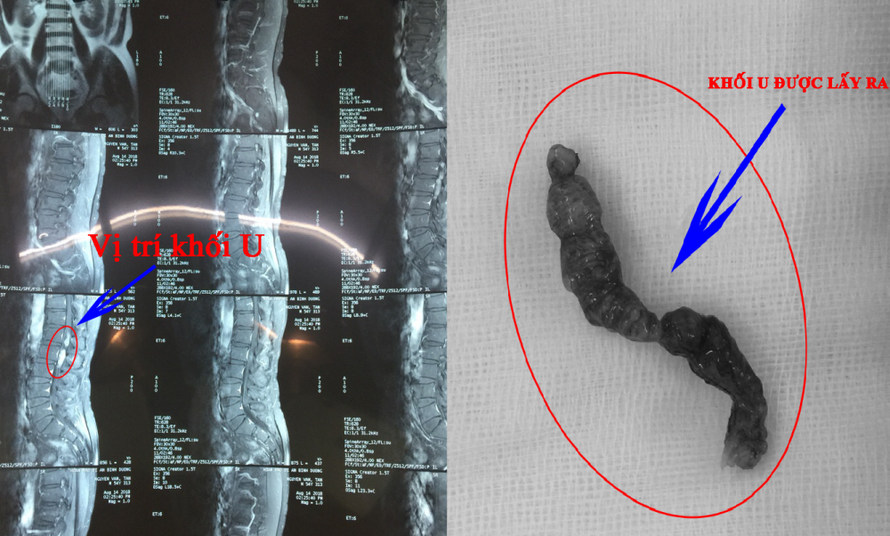

Khối U nằm trong tủy sống bệnh nhân - Ảnh: VTC News

Thông tin từ VTC News cho biết, vừa qua, bệnh viện quận Thủ Đức (TP.HCM) đã thực hiện thành công ca phẫu thuật lấy khối u tủy cột sống dài gần 10 cm cho bệnh nhân N.N.T (54 tuổi, ngụ Dĩ An, Bình Dương).

Trước đó, ngày 15/8, bệnh nhân N.N.T nhập viện trong tình trạng tay chân co cứng, lưng đau, chân phải bị tê không đi lại được. Các bác sỹ tại bệnh viện chẩn đoán bệnh nhân bị u tủy sống đoạn L1-L2, L2-L3. Ngay lập tức, bệnh nhân được chuyển lên khoa Ngoại Thần Kinh phẫu thuật lấy khối u ra.

Trao đổi với báo Người Lao Động, BS Trương Long Vỹ, Trưởng Khoa Ngoại Thần kinh Bệnh viện quận Thủ Đức, người trực tiếp phẫu thuật cho biết, đây là ca phẫu thuật khó. Bệnh nhân có khối u có kích thước lớn và dài (khoảng 10 cm), nằm ngay tại vị trí chóp tủy nên ê kíp phải hết sức cẩn trọng, nếu không thì rất dễ gây tai biến dẫn tới bệnh nhân bị liệt hoàn toàn.